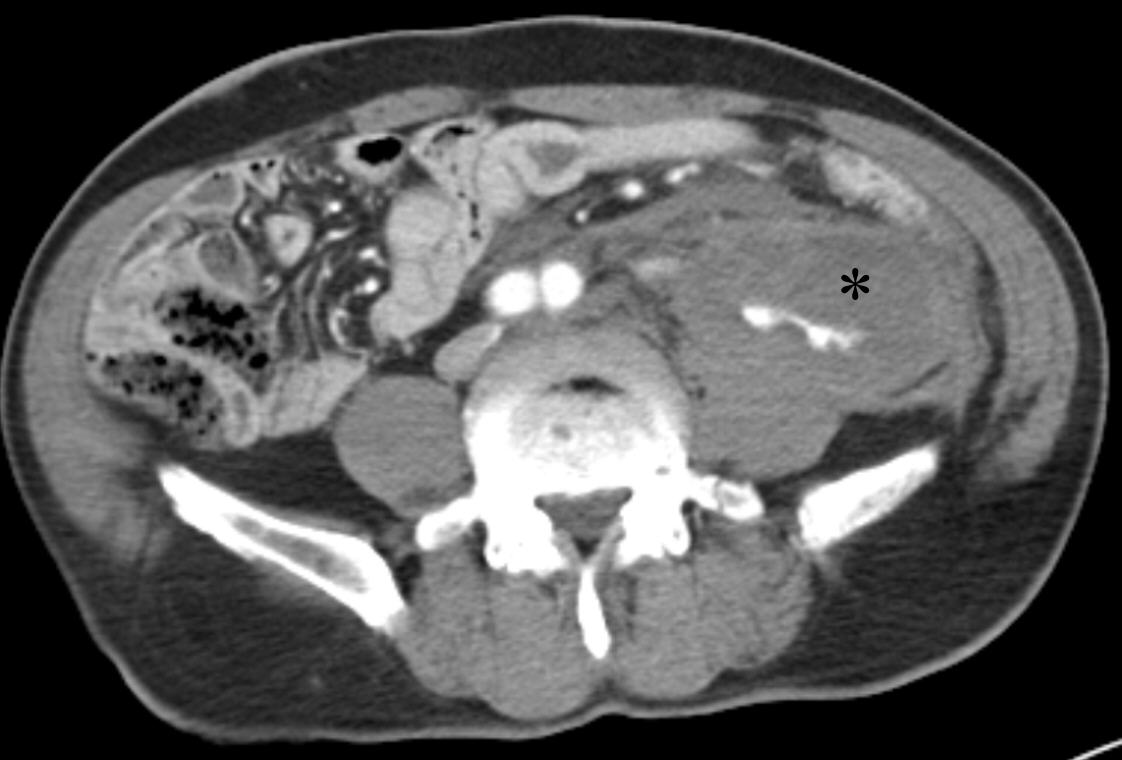

Following the procedure, the patient’s blood pressure normalized. One month later, a delayed-phase abdominopelvic CT demonstrated embolic material tracking along the course of the left ureter. Notably, when the retroperitoneal hematoma was large, the left ureteric artery appeared to originate at the 12 o’clock position; however, as the hematoma decreased, the origin of the artery was observed to shift to the 3 o’clock position (

Fig. 3). During the three-month follow-up period, the patient developed distal ureteral stenosis, which was suspected to result from the ureteric artery embolization. The patient is currently under urological outpatient follow-up with a double-J stent in situ.

Fig. 4). Anatomically, the ureteric artery typically originates laterally from the abdominal aorta. However, in the present case, it appeared to originate anteriorly due to displacement caused by a surrounding hematoma. On follow-up computed tomography, after resolution of the hematoma, the artery was again visualized as originating laterally. This case underscores that an exclusive assumption of a lateral origin from the abdominal aorta may impede the precise identification of the ureteric artery in certain clinical contexts.

Fig. 3.Follow-up CT after hematoma reduction shows the embolized left ureteric artery (arrow) as a hyperdense structure due to the presence of embolic materials. With the hematoma resolved, the artery appears to originate laterally.